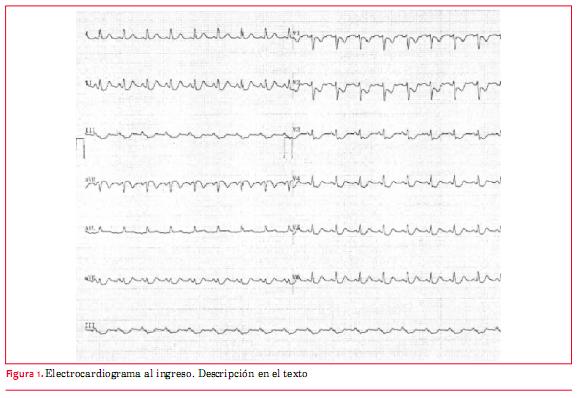

Se realiza electrocardiograma (ECG) (figura 1) que muestra injuria subepicárdica de sectores lateral y posterior. No se realizan derivadas posteriores.

Se inicia tratamiento médico en base a ácido acetilsalicílico (AAS), clopidogrel en dosis carga y NTG intravenoso, con persistencia del dolor y de las alteraciones en el ECG. Se inicia estreptoquinasa intravenosa 1.500.000 unidades a los 90 minutos del inicio del dolor. No presenta criterios de reperfusión clínicos ni electrocardiográficos.

Se realiza angioplastia de arteria circunfleja y primer ramo marginal con stent Promus Premier 3,5 por 28 mm y stent Promus Premier 2,5 por16 mm, respectivamente, con buen resultado angiográfico (figura 3), alivio del dolor y normalización del ECG (figura 4).